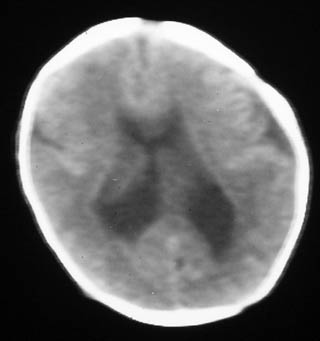

透明隔缺如

透明隔缺如。

这是一个早产儿(大约34周左右)的片子,可以是透明隔缺如,但往往是错误的。

视-隔发育不良:视-隔发育不良是罕见的中线结构前部畸形,主要特征为透明隔缺如,一般常见于垂体性侏儒症。ct表现为正常的透明隔缺如,双侧侧脑室前角及体部融合为一单脑室,侧脑室及第三脑室中度扩大,侧脑室前角在轴位像上呈反三角形,胼胝体压部变薄。约半数患者还伴有其它脑裂畸形改变。

胼胝体发育不全:胼胝体发育不全病因未完全确定,与遗传因素、母体感染或血管因素有关。胼胝体发育不全还可合并半球间裂囊肿、脂肪瘤、透明隔发育不全等。ct表现:半球间裂过深,第三脑室向前上移位,两侧侧脑室扩大,体部分离,呈反“八”字型或平行状。可伴随脑裂畸形、巨脑回、半脑间裂、蛛网膜囊肿及透明隔缺如等

透明隔缺如,支持。